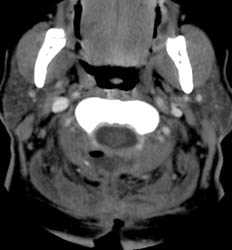

Contrast enhanced axial CT scan demonstrates unroofing

of the spinal canal from the C2 to the C7 with bilateral laminectomies and

removal of the spinous processes. There is a fluid collection without

significant rim enhancement in the post surgical bed at the C2 level,

posterior to the spinal canal. Within this, there is some air. The fluid

collection appears to extend inferiorly to the C3 level, and then a small

slit of fluid continues inferiorly to the C5 - 6 level (not shown), where it appears

to communicate with the midline incision . |